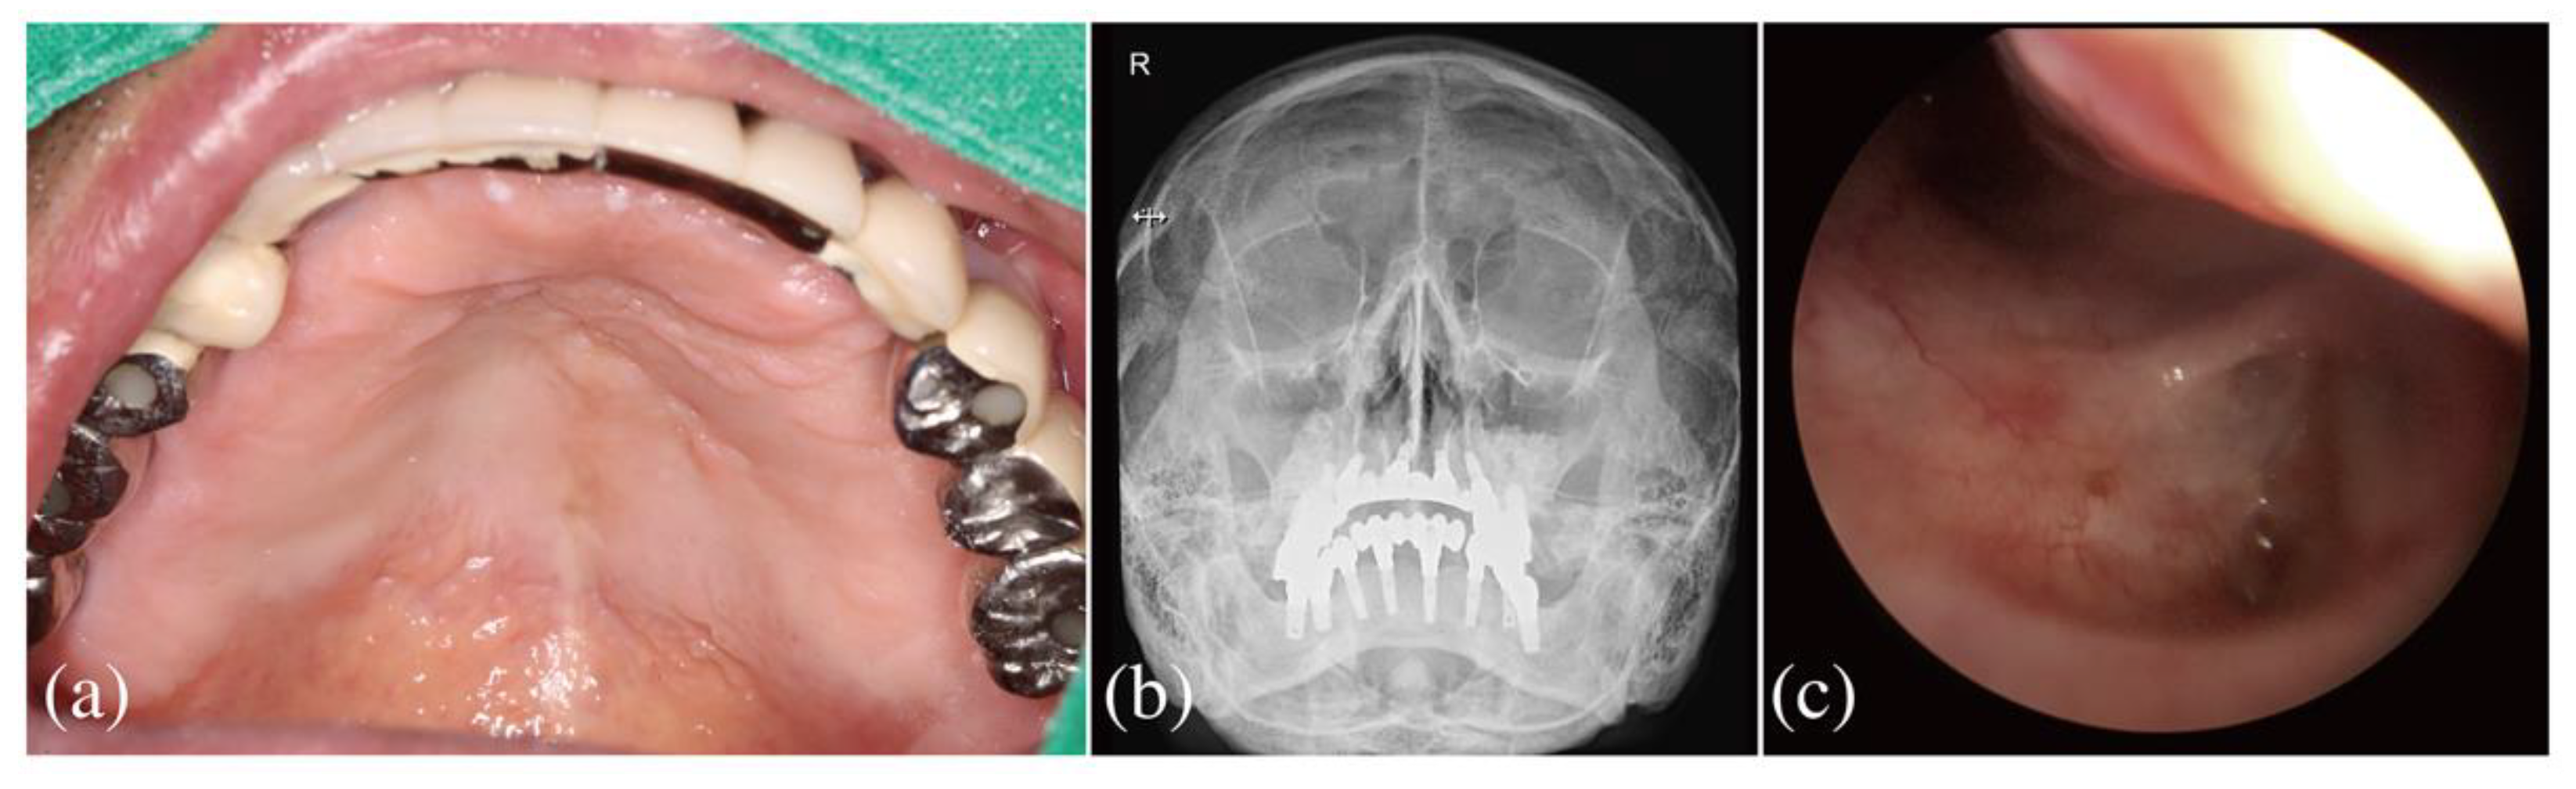

2.2. Dental Examination

2.3. Referral to an Otolaryngological Specialist